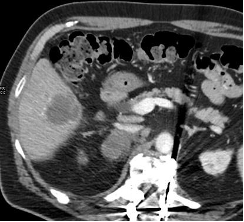

Index Procedure: The subject underwent TAE with Embrace HES under monitored anesthesia care (MAC). Left transradial access was obtained. A coaxial microcatheter system with a 1.7F 162-cm microcatheter (Instylla) inserted in a 2.8F 150-cm microcatheter (Progreat®, Terumo Medical Corporation) was used to embolize a single 3-mm feeder vessel with 1.6 mL of the Embrace (Figure 1). There was no clinical evidence of non-target embolization. Follow-Up: Repeat computed tomography performed at 30- and 90-days post index procedure indicated no evidence of revascularization and no local tumor progression (Figure 2). An independent Core Lab assessed a complete response in accordance with mRECIST criteria at both timepoints.